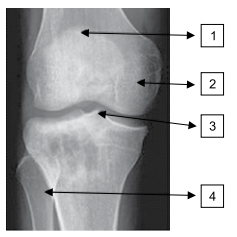

As estruturas assinaladas correspondem a qual alternativa?